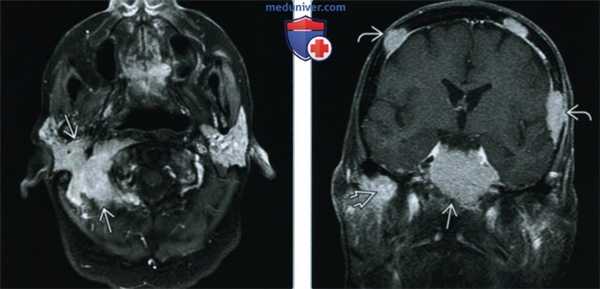

(Слева) При МРТ Т1FS c КУ в аксиальной проекции у пациента с парезом правого лицевого нерва определяется равномерно контрастируемая опухоль, состоящая из костного и внекостного компонентов, вызывающая деструкцию сосцевидного отростка правой височной кости и облитерирующая шилососцевидное отверстие. МРТ T1 FS с КУ, как правило, является наиболее чувствительной методикой диагностики поражения костного мозга.

(Справа) При корональной МРТ Т1FS с КУ определяется контрастное основное объемное образование ската затылочной кости и более мелкие миеломатозные новообразования свода черепа и правой нижневисочной ямки.